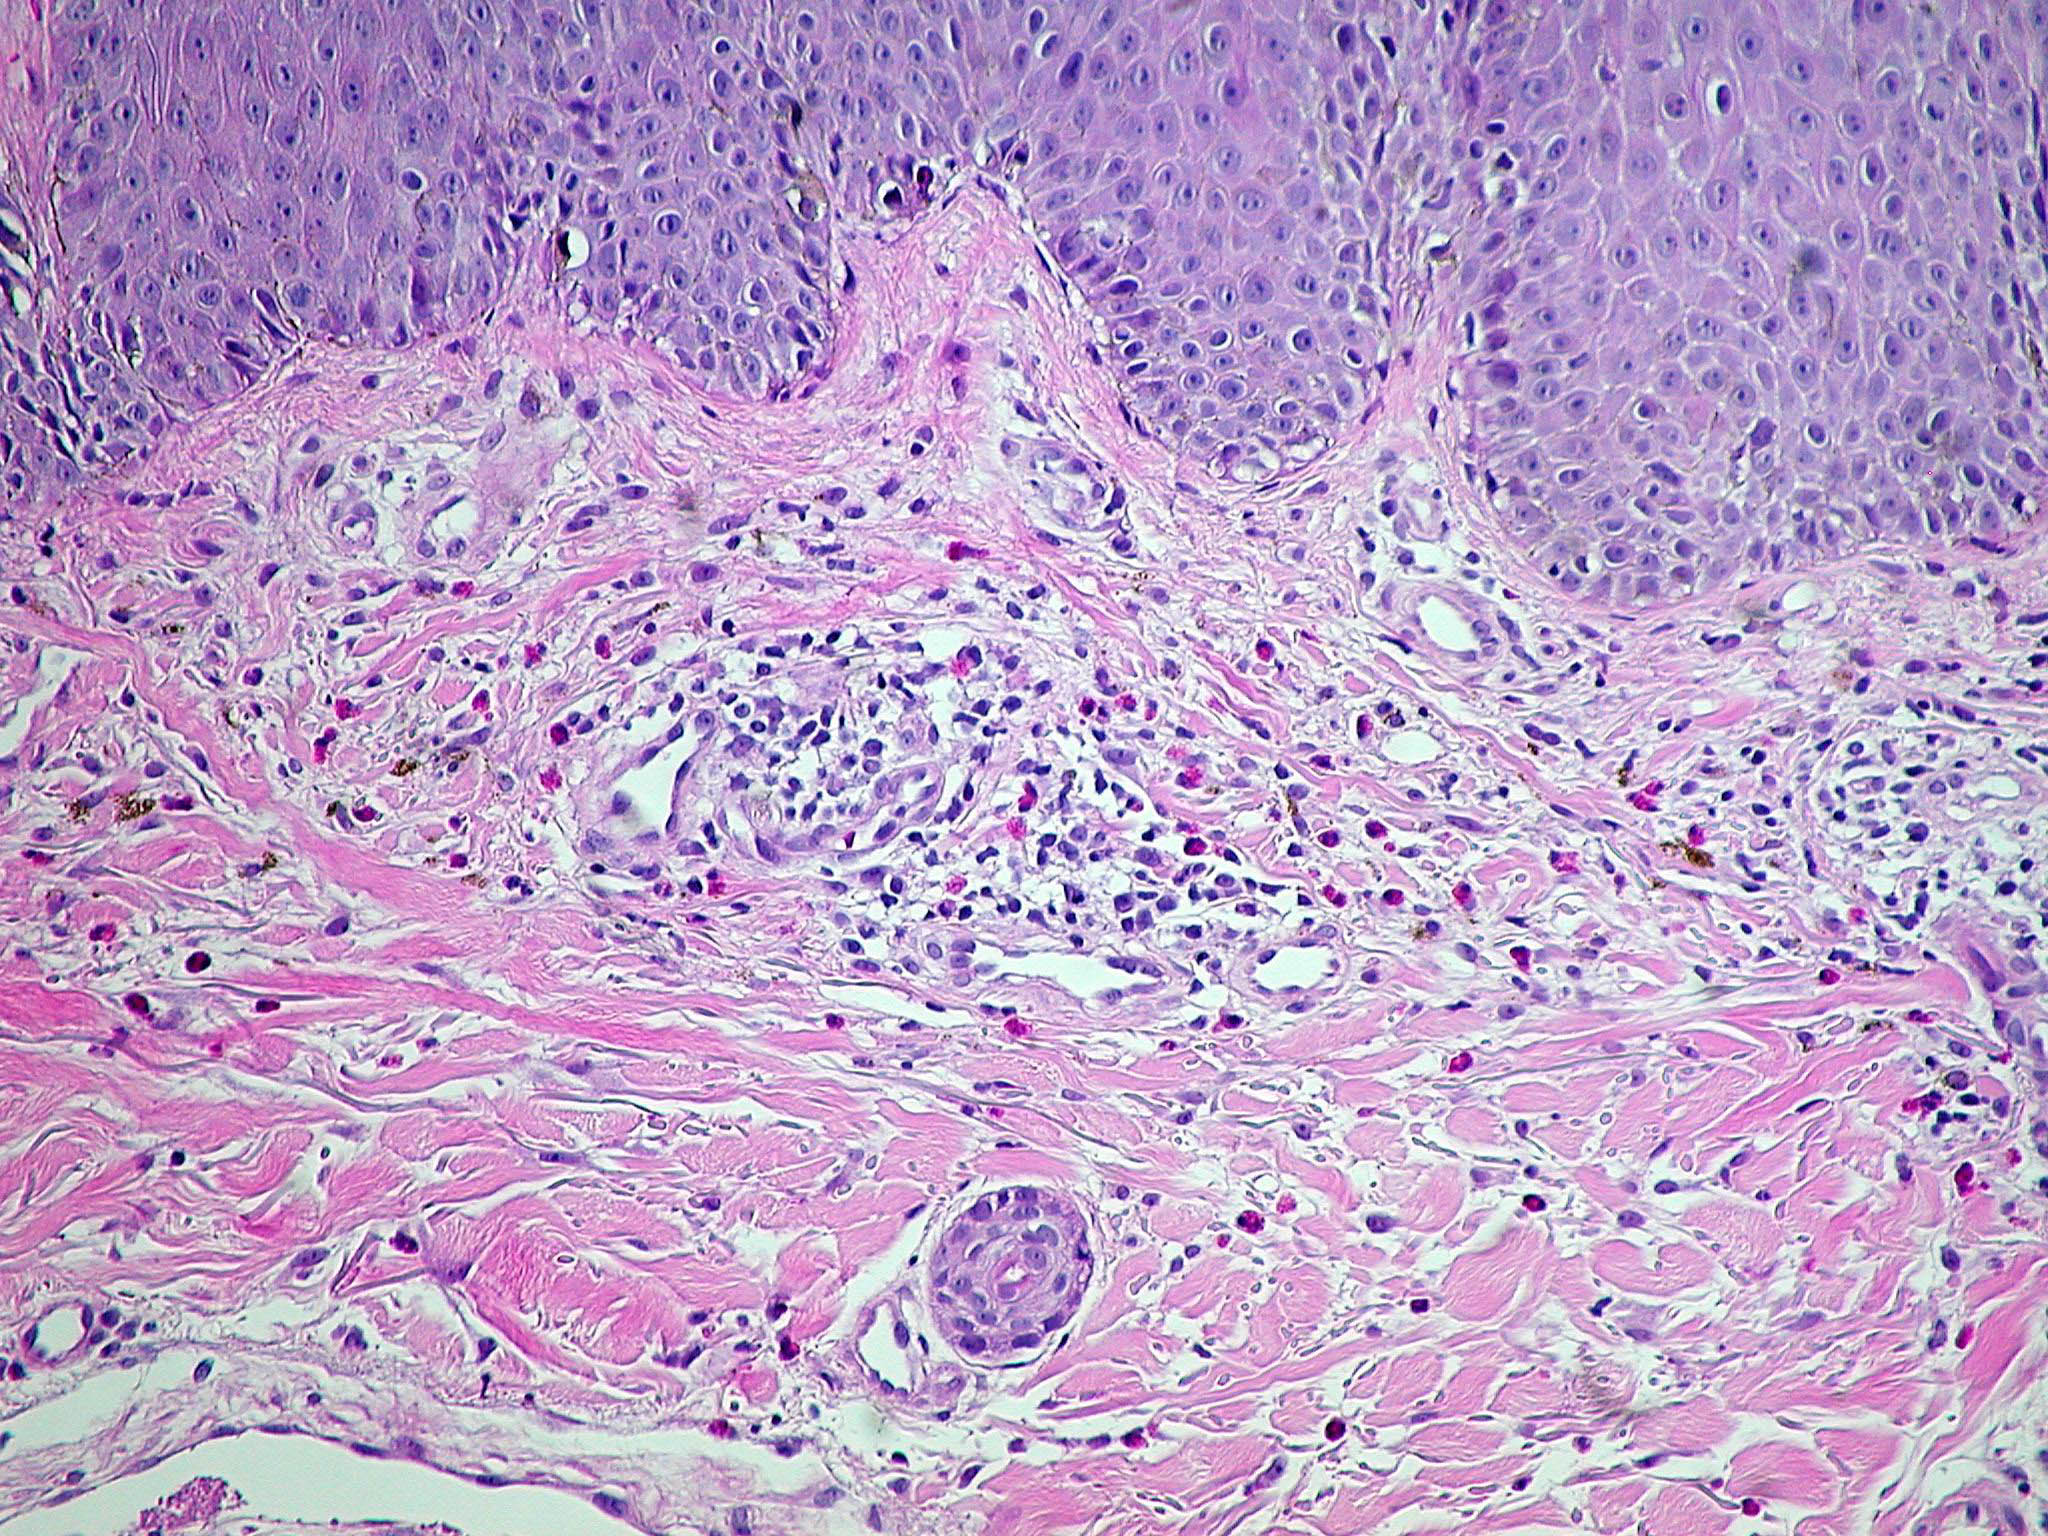

Psoriasis Vulgaris Histopathology The histologic picture of psoriasis vulgaris varies considerably with the stage of the lesion and usually is diagnostic only in early, scaling papules and near the margin of advancing plaques. |

The earliest pinhead-sized macules or smooth-surfaced papules show subtle histologic changes with a preponderance of dermal changes . At first, there is capillary dilation and edema in the papillary dermis, with a lymphocytic infiltrate surrounding the capillaries. The lymphocytes extend to the lower portion of the epidermis, where slight spongiosis develops. Then focal changes occur in the upper portion of the epidermis, where granular cells become vacuolated and disappear, and mounds of parakeratosis are formed. Neutrophils are usually seen only at the summits of some of the mounds of parakeratosis and appear scattered through an otherwise orthokeratotic cornified layer . These mounds of parakeratosis with neutrophils represent the earliest manifestation of Munro microabscesses . At this stage, which is characterized clinically by an early scaling papule, a histologic diagnosis of psoriasis can often be made. In some cases, when there is marked |

exocytosis of neutrophils, they may aggregate in the uppermost portion of the spinous layer to form small spongiform pustules of Kogoj. Lymphocytes remain confined to the lower epidermis, which, as more and more mitoses occur, becomes increasingly hyperplastic. The epidermal changes are at first focal, but later become confluent, leading clinically to plaques. In the fully developed lesions of psoriasis, as best seen at the margin of enlarging plaques, the histologic picture is characterized by (a) acanthosis with regular elongation of the rete ridges with thickening in their lower portion; (b) thinning of the suprapapillary epidermis with the occasional presence of small spongiform pustules; (c) pallor of the upper layers of the epidermis; (d) diminished to absent granular layer; (e) confluent parakeratosis; (f) the presence of Munro microabscesses; (g) elongation and edema of the dermal papillae; and (h) dilated and tortuous capillaries . |

Of the listed features, only the spongiform pustules of Kogoj and Munro microabscesses are truly diagnostic of psoriasis, and, in their absence, the diagnosis can rarely be made with certainty on a histologic basis. The changes in active psoriasis are discussed in detail later. |

The rete ridges show considerable elongation and extend downward to a uniform level, resulting in regular acanthosis . They are often slender in their upper portion but |

show thickening ("clubbing") in their lower portion. Not infrequently, adjacent rete ridges seem to coalesce at their bases due to tangential sectioning. Usually, intercellular and intracellular edema is absent in the rete ridges, and keratinocytes located well above the basal layer show deep basophilia. In addition, mitoses are not limited to the basal layer as in normal skin but are also seen above the basal layer. This, together with a considerable lengthening of the basal cell layer due to elongation of the rete ridges, results in a marked increase in the number of mitoses. This increase has been calculated to be 27 times the number of mitoses in uninvolved skin . |

The suprapapillary epidermis appears relatively thin in comparison with the markedly elongated rete ridges, and the cells in the upper layers of the epidermis may appear enlarged and pale stained as a result of intracellular edema and hypogranulosis. Keratinocytes beneath the parakeratotic cornified layer may be intermingled with neutrophils . The histologic picture is then that of a small spongiform pustule of Kogoj . Although it is only a micropustule, it is nevertheless of the same type as the much larger macropustules seen in pustular psoriasis. Such a spongiform pustule, highly diagnostic for psoriasis and its variants, shows aggregates of neutrophils within the interstices of a spongelike network formed by degenerated and thinned epidermal cells |

In some instances the cornified layer consists entirely of confluent parakeratosis forming a platelike scale with a concomitant absence or diminution of the granular layer. However, occasional focal orthokeratosis with preservation of the underlying granular cells is present. |

Munro microabscesses are located within the parakeratotic areas of the cornified layer . They consist of accumulations of neutrophils and pyknotic nuclei of neutrophils that have migrated there from capillaries in the papillae through the suprapapillary epidermis. As a rule, Munro microabscesses are easily found in early lesions but are few in number or absent in longstanding lesions . The dermal papillae, in accordance with the elongation and basal thickening of the rete ridges, are elongated and club shaped. They show edema, and the capillaries within them appear dilated and tortuous. A relatively mild inflammatory infiltrate is present in the upper dermis and the papillae. It consists of lymphocytes, except in early lesions, in which neutrophils are also present in the upper portion of the papillae . |